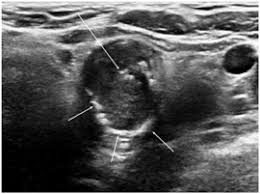

Ultrasound

ID: 2565fe9a-bd55-4307-a30a-7cb752afafe3...2565fe9a-bd55-4307-a30a-7cb752afafe3

29 yoshli Erkak

30.10.2025 10:38

Yuqori

Tashxis

Malignant (Xavfli)

Saraton xavfi - Shifokorga murojaat qiling!

Ishonch

72,3%

TSH

1,83

Tugun

4,05 sm

Yuklab olingan (26x)

Ko'rish